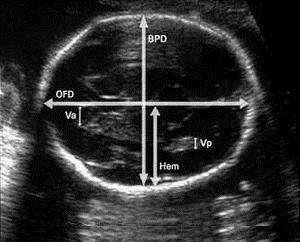

Вимірює БПР плода фахівець з УЗД. Робиться вимір в напрямку від скроні до скроні. Якщо лікар візьме неправильна відстань, не врахує, що лінія, що з'єднує контури скронь, повинна бути чітко над таламуса, то він може отримати далекі від вірних результати. Далі вимірюється лобно-потилична частина, яку вимірюють від чола до потилиці дитини.

BPD - УЗД знімок, який показує біпаріетальний розмір

Розміри BPD на узі (БПР)